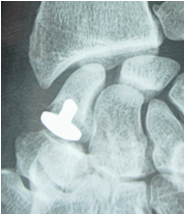

In fact, the patient is usually more bothered by the osteosynthesis material and can often ask for it to be removed. This is why my preferred technique is resurfacing the distal pole of scaphoid using an INCA™ prosthesis (Groupe Lepine). The procedure is quick and easy and can be performed through an anterior portal. The outcomes are good, with mild or zero pain and good finger opposition. Figure 6.